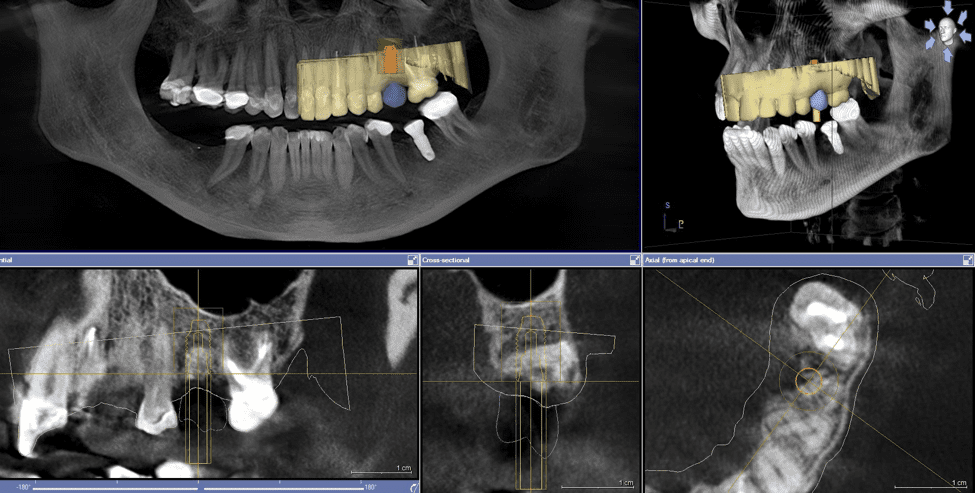

Με την αξονική τομογραφία άνω ή κάτω γνάθου, γνωστή επίσης ως Dental Scan ή CBCT, ο οδοντίατρος λαμβάνει αναλυτικές πληροφορίες καθώς η απεικόνιση είναι τρισδιάστατη (3D) την στιγμή που σε μια απλή πανοραμική ακτινογραφία η απεικόνιση είναι δισδιάστατη (2D).

Λήψη πληροφοριών σχετικά με τον αριθμό και την θέση που θα τοποθετηθούν τα οδοντικά εμφυτεύματα, την ανάγκη οστικής ανάπλασης, την πυκνότητα του οστού της γνάθου, την θέση του φατνιακού νεύρου και του ιγμορείου.

Επιπρόσθετα ο συνδυασμός του με τον ενδοστοματικό σαρωτή βοηθά στην δημιουργία χειρουργικού νάρθηκα για την καθοδηγούμενη τοποθέτηση των εμφυτευμάτων.